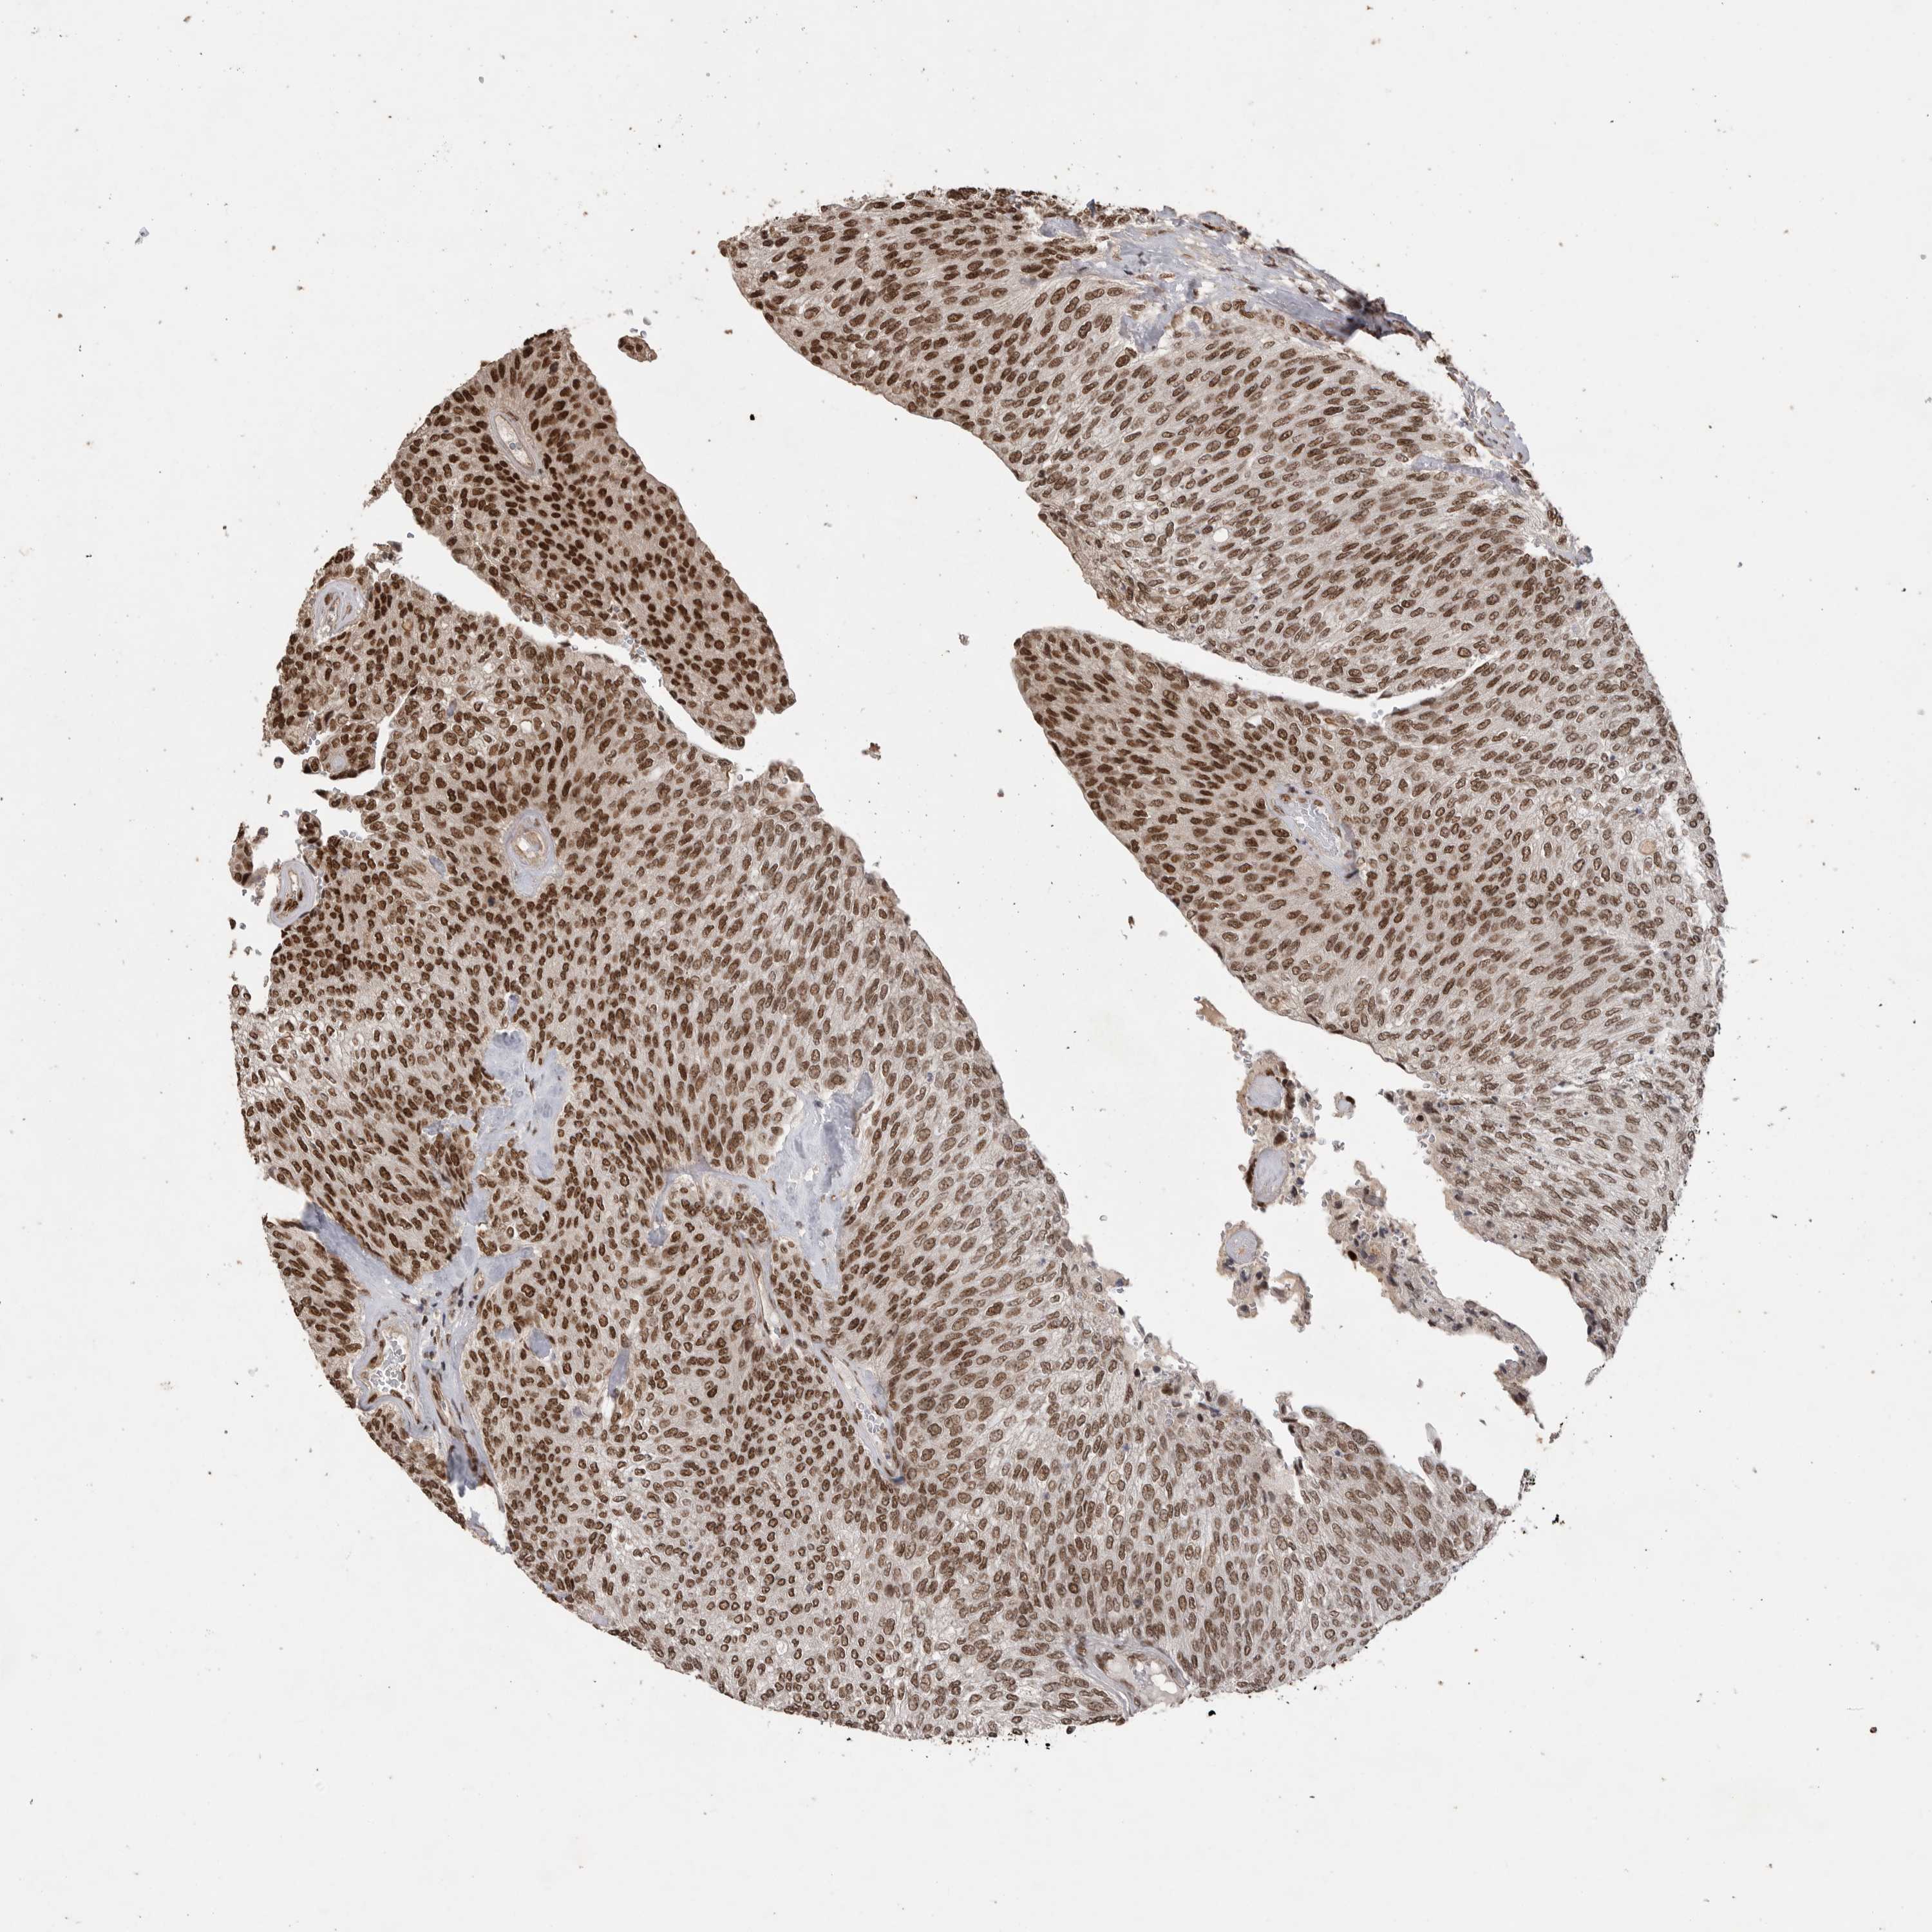

UROTHELIAL CANCER - Protein expressioni

A mouse-over function shows sample information and annotation data. Click on an image to view it in a full screen mode. Samples can be filtered based on level of antibody staining by selecting one or several of the following categories: high, medium, low and not detected. The assay and annotation is described here.

Note that samples used for immunohistochemistry by the Human Protein Atlas do not correspond to samples in the TCGA dataset.

Antibody stainingi

Antibody staining in the annotated cell types in the current human tissue is reported as not detected, low, medium, or high, based on conventional immunohistochemistry profiling in selected tissues. This score is based on the combination of the staining intensity and fraction of stained cells.

Each image is clickable and will lead to virtual microscopy that enables deeper exploration of all samples and also displays staining intensity scores, fraction scores and subcellular localization as well as patient and tissue information for each sample.

Antibody HPA027406

Antibody HPA027417

Antibody HPA027452

Staining

High

Medium

Low

Not detected

Intensity

Strong

Moderate

Weak

Negative

Quantity

>75%

75%-25%

<25%

None

Location

Nuclear

Cytoplasmic/membranous

Cytoplasmic/membranous,nuclear

Urothelial carcinoma, Low grade

Urothelial carcinoma, High grade